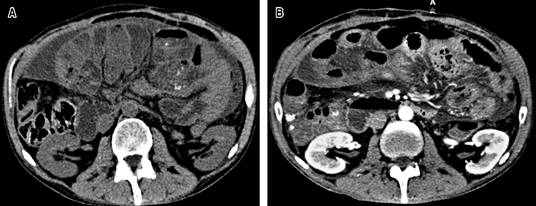

Se ingresa a hospitalización y por sospecha de oclusión secundario a adherencias se decide manejo conservador a base de reposo intestinal, sonda nasogástrica y fluidoterapia con cristaloide, sin embargo, por persistencia de la sintomatología y aumento del dolor abdominal se solicita tomografía abdominopélvica simple reportando distensión de asas de intestino delgado, con punto máximo de dilatación en íleon terminal, así como edema de pared y estriaciones concéntricas por probable intususcepción (Figura 1).

Figura 1: Fotos de tomografía computarizada. A) Tomografía simple que informa ascitis en compartimentos y líquido libre interasa. B) Tomografía con contraste intravenoso que evidencia sobredistensión de asas de intestino delgado, contenido predominantemente líquido y alcanzando máxima dilatación hacia íleon terminal, donde se observa engrosamiento de pared y estriaciones concéntricas.